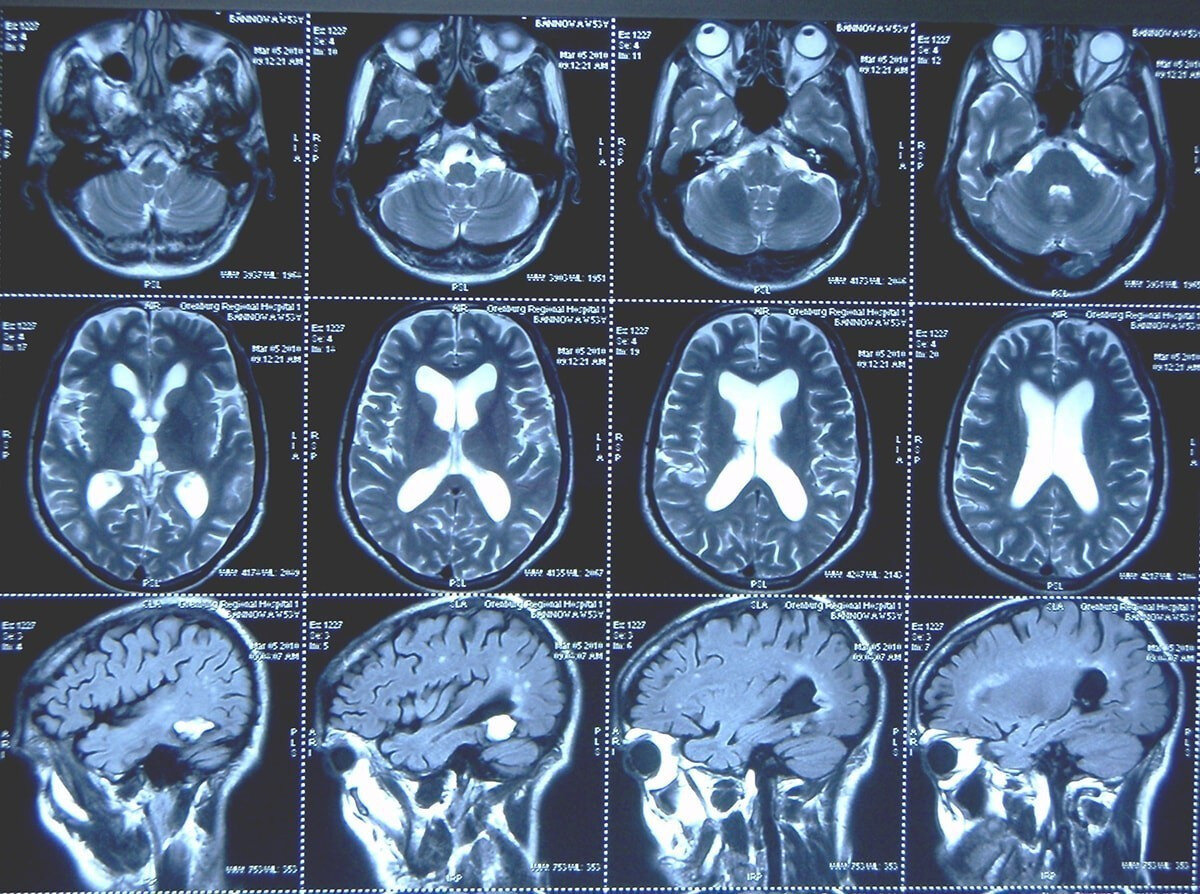

В 1985 году группа американских ученых инициировала изучения головного мозга. Для исследования были выбраны 150 добровольцев. Им провели МРТ, сделали тесты и анализы, собрали анамнез.

Повторное обследование мозга и всего организма испытуемые прошли спустя 25 лет, когда участникам исполнилось 55 лет и больше. Проанализировав результаты, медики установили, что ряд серьезных отклонений в здоровье действительно могут стать причиной преждевременной деменции в старшем возрасте.